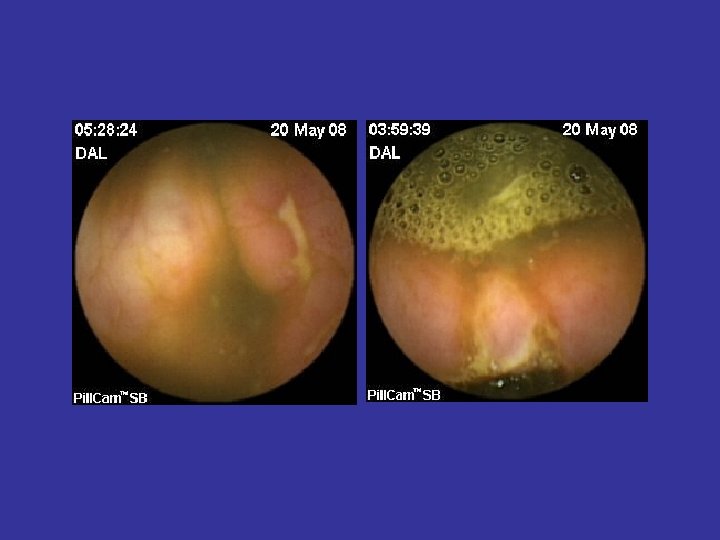

Hemoragia digestiva de cauza obscura (OGIB) • Indicatia majora a WCE • Acuratete diagnostica superioara (~ dubla) tuturor celorlalte metode diagnostice (Rx, PE, DBE, etc) • Administrare cat mai precoce dupa episodul hemoragic (< 48 ore) • WCE: rol in orientarea managementului si ameliorarea prognosticului • Repetarea WCE dupa un examen negativ creste acuratetea diagnostica

Tipuri de leziuni depistate in BC • • Eroziuni Edem mucosal Congestie parcelara Ulceratii aftoide; Ulcere liniare/ neregulate/ confluente; Pseudopolipi inflamatori; Stenoze inflamatorii;